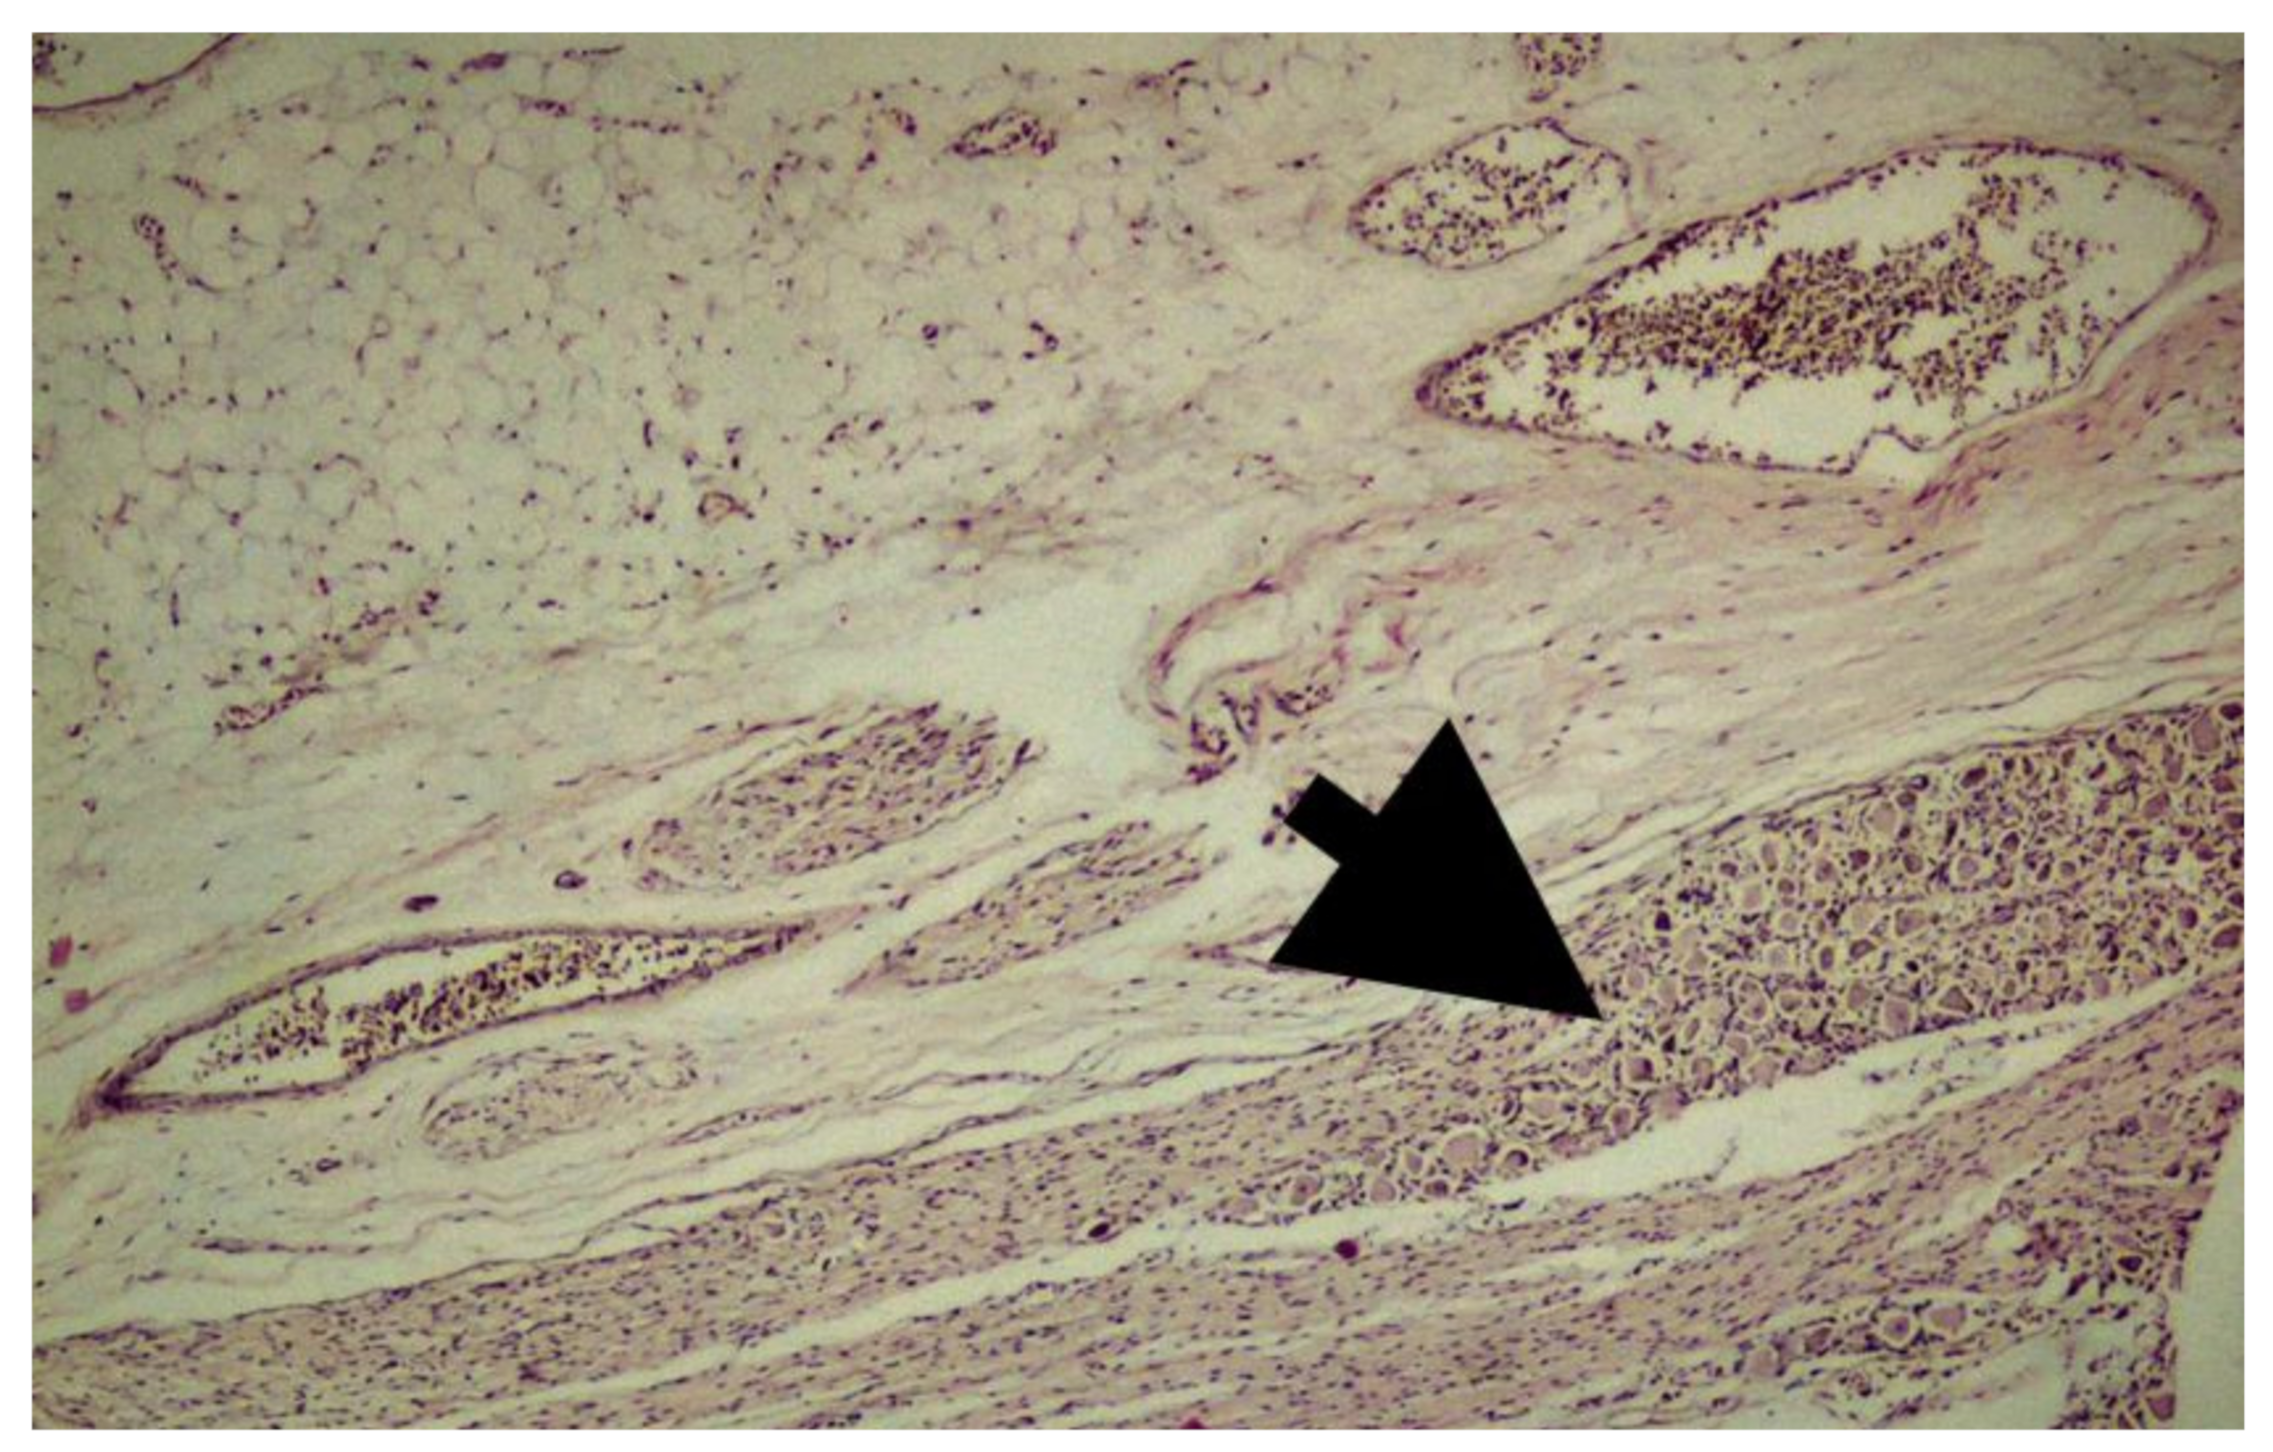

- Tehli, O.; Hodaj, I.; Kural, C.; Solmaz, I.; Onguru, O.; Izci, Y. A comparative study of histopathological analysis of filum terminale in patients with tethered cord syndrome and in normal human fetuses. Pediatr. Neurosurg. 2011, 47, 412–416. [Google Scholar] [CrossRef]

- Kural, C.; Guresci, S.; Simsek, G.G.; Arslan, E.; Tehli, O.; Solmaz, I.; Izci, Y. Histological structure of filum terminale in human fetuses. J. Neurosurg. Pediatr. 2014, 13, 362–367. [Google Scholar] [CrossRef]

- Hendson, G.; Dunham, C.; Steinbok, P. Histopathology of the filum terminale in children with and without tethered cord syndrome with attention to the elastic tissue within the filum. Childs Nerv. Syst. 2016, 32, 1683–1692. [Google Scholar] [CrossRef] [PubMed]